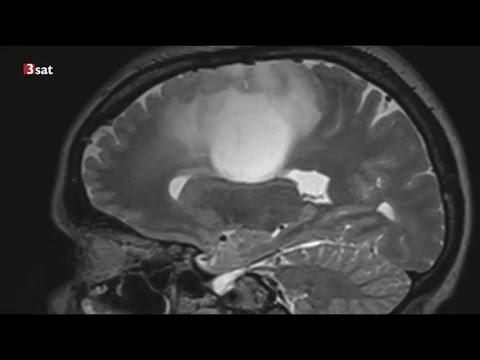

Methadon medizinisch erklärt durch Dr. med. Dietmar Peikert (Glioblastom 4) Video 8 (engl. Sub.)